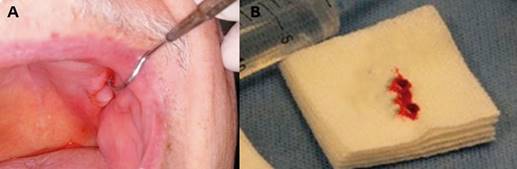

The first clinical examination found no evidence of facial asymmetries or volume increase (Fig. 1). The patient was completely edentulous and had a linear discontinuity at the mucosa of the left maxillary alveolar ridge of approximately 1 cm in diameter. It extended from the edentulous region of teeth 2.5-2.7 to the maxillary tuberosity. Clearly delimited lesion, with abundant bleeding and purulent exudate. Large edema and erythema of the surrounding soft tissues were also observed (Fig. 2). Communication with bone tissue was confirmed by probing the lesion and removing the remaining necrotic bone tissue and abundant hematic content (Fig. 3 A, B).

Fig. 3: (A) Intraoral view showing communication with the bone. (B) The remaining necrotic bone tissue was removed during probing.